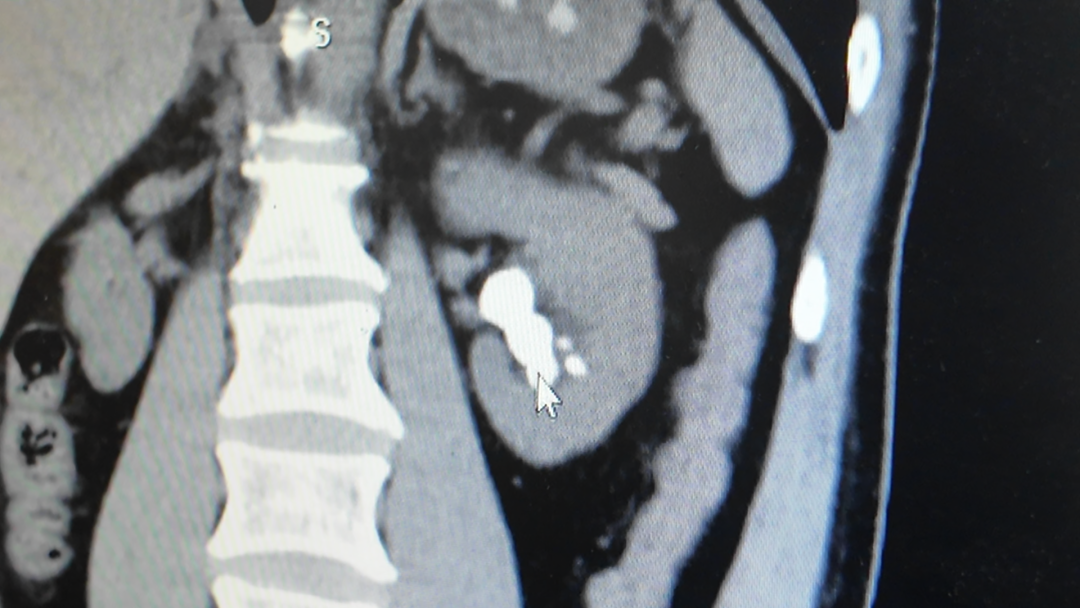

近年来,泌尿系结石在全球的发病率持续上升,其中尿路结石发作时的剧痛让不少人难以忍受,部分患者的疼痛程度甚至超过分娩

近日,市民李先生突然尿血,到亭林医院检查后确诊为尿路结石。就在办理住院的前一晚,他腰腹部突发剧痛,紧急急诊入院并需立即手术